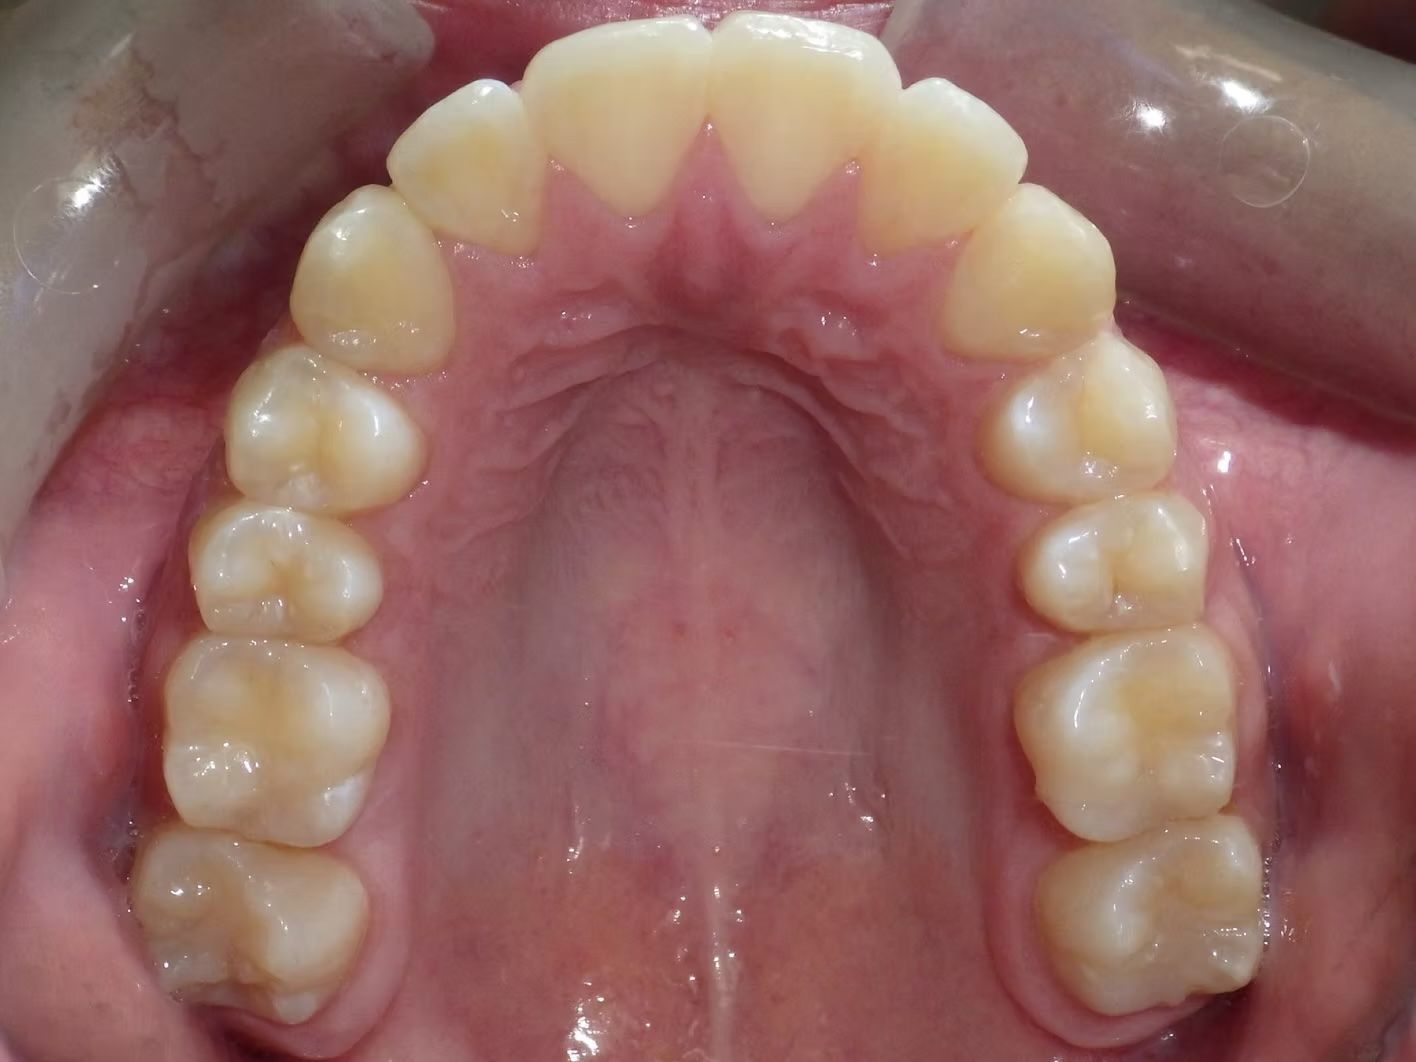

Maribel began treatment with Dr. Bret because she couldn't chew food with her front teeth. She had an anterior open bite with severe crowding of her upper and lower teeth. She was treated with the removal of 4 premolar teeth - 2 in the top and two lower premolars and we were able to get her front teeth to line up beautifully- she can't stop smiling.

Click on the images below to enlarge them.